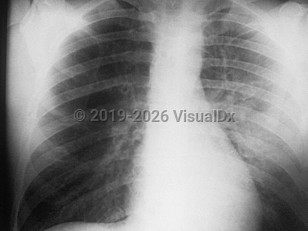

EVALI

COVID-19

Drug-induced pneumonitis